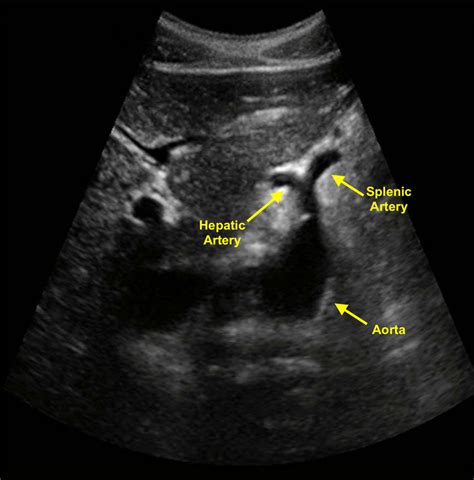

Ultrasound: Uses sound waves to create images of the abdomen. It is non-invasive and can detect aneurysms, but it may not provide detailed images.